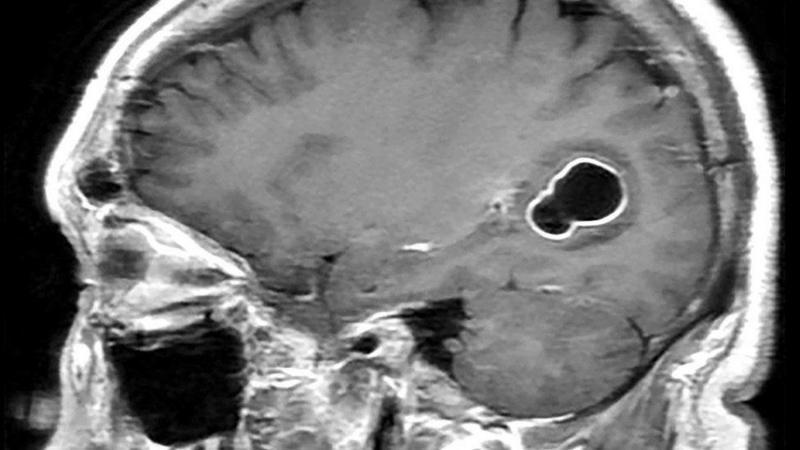

LEE TAMBIÉN Fue al médico por migrañas y lo que descubrieron en su cerebro los dejó sorprendidos